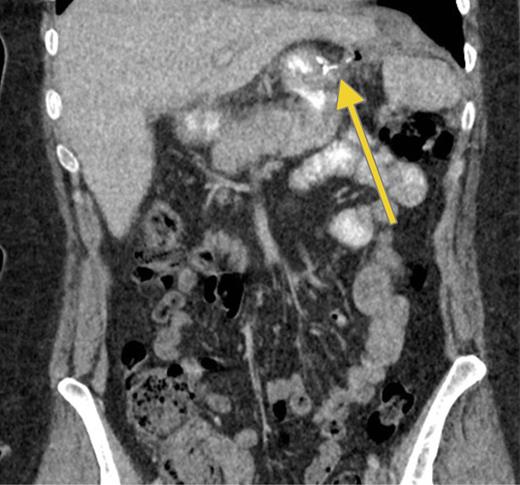

In December, the patient presented with abdominal pain and a palpable left upper quadrant mass. CT showed extravasation of oral contrast from the proximal site of the gastric sleeve in communication with a sub-left diaphragmatic collection (Fig. 4).

Recurrence. Computed tomography scan with oral contrast demonstrating a persistent small leak (arrow) 3 weeks after a negative GS.